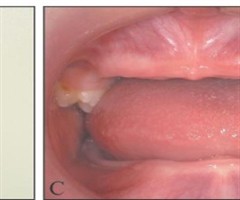

年轻恒牙复杂冠根折伴根折树脂短桩固位行断冠再粘接1例

[摘要]本病例报告了1例9岁儿童上颌中切牙复杂冠根折伴发根折的断冠再接治疗。治疗策略遵循微创原则从活髓保存、根折愈合、牙冠修复三个方面出发,通过树脂短桩增强固位进行断冠再粘接实现了前牙的美学修复和功能重建。经过2年的随访,临床及影像学均展示...